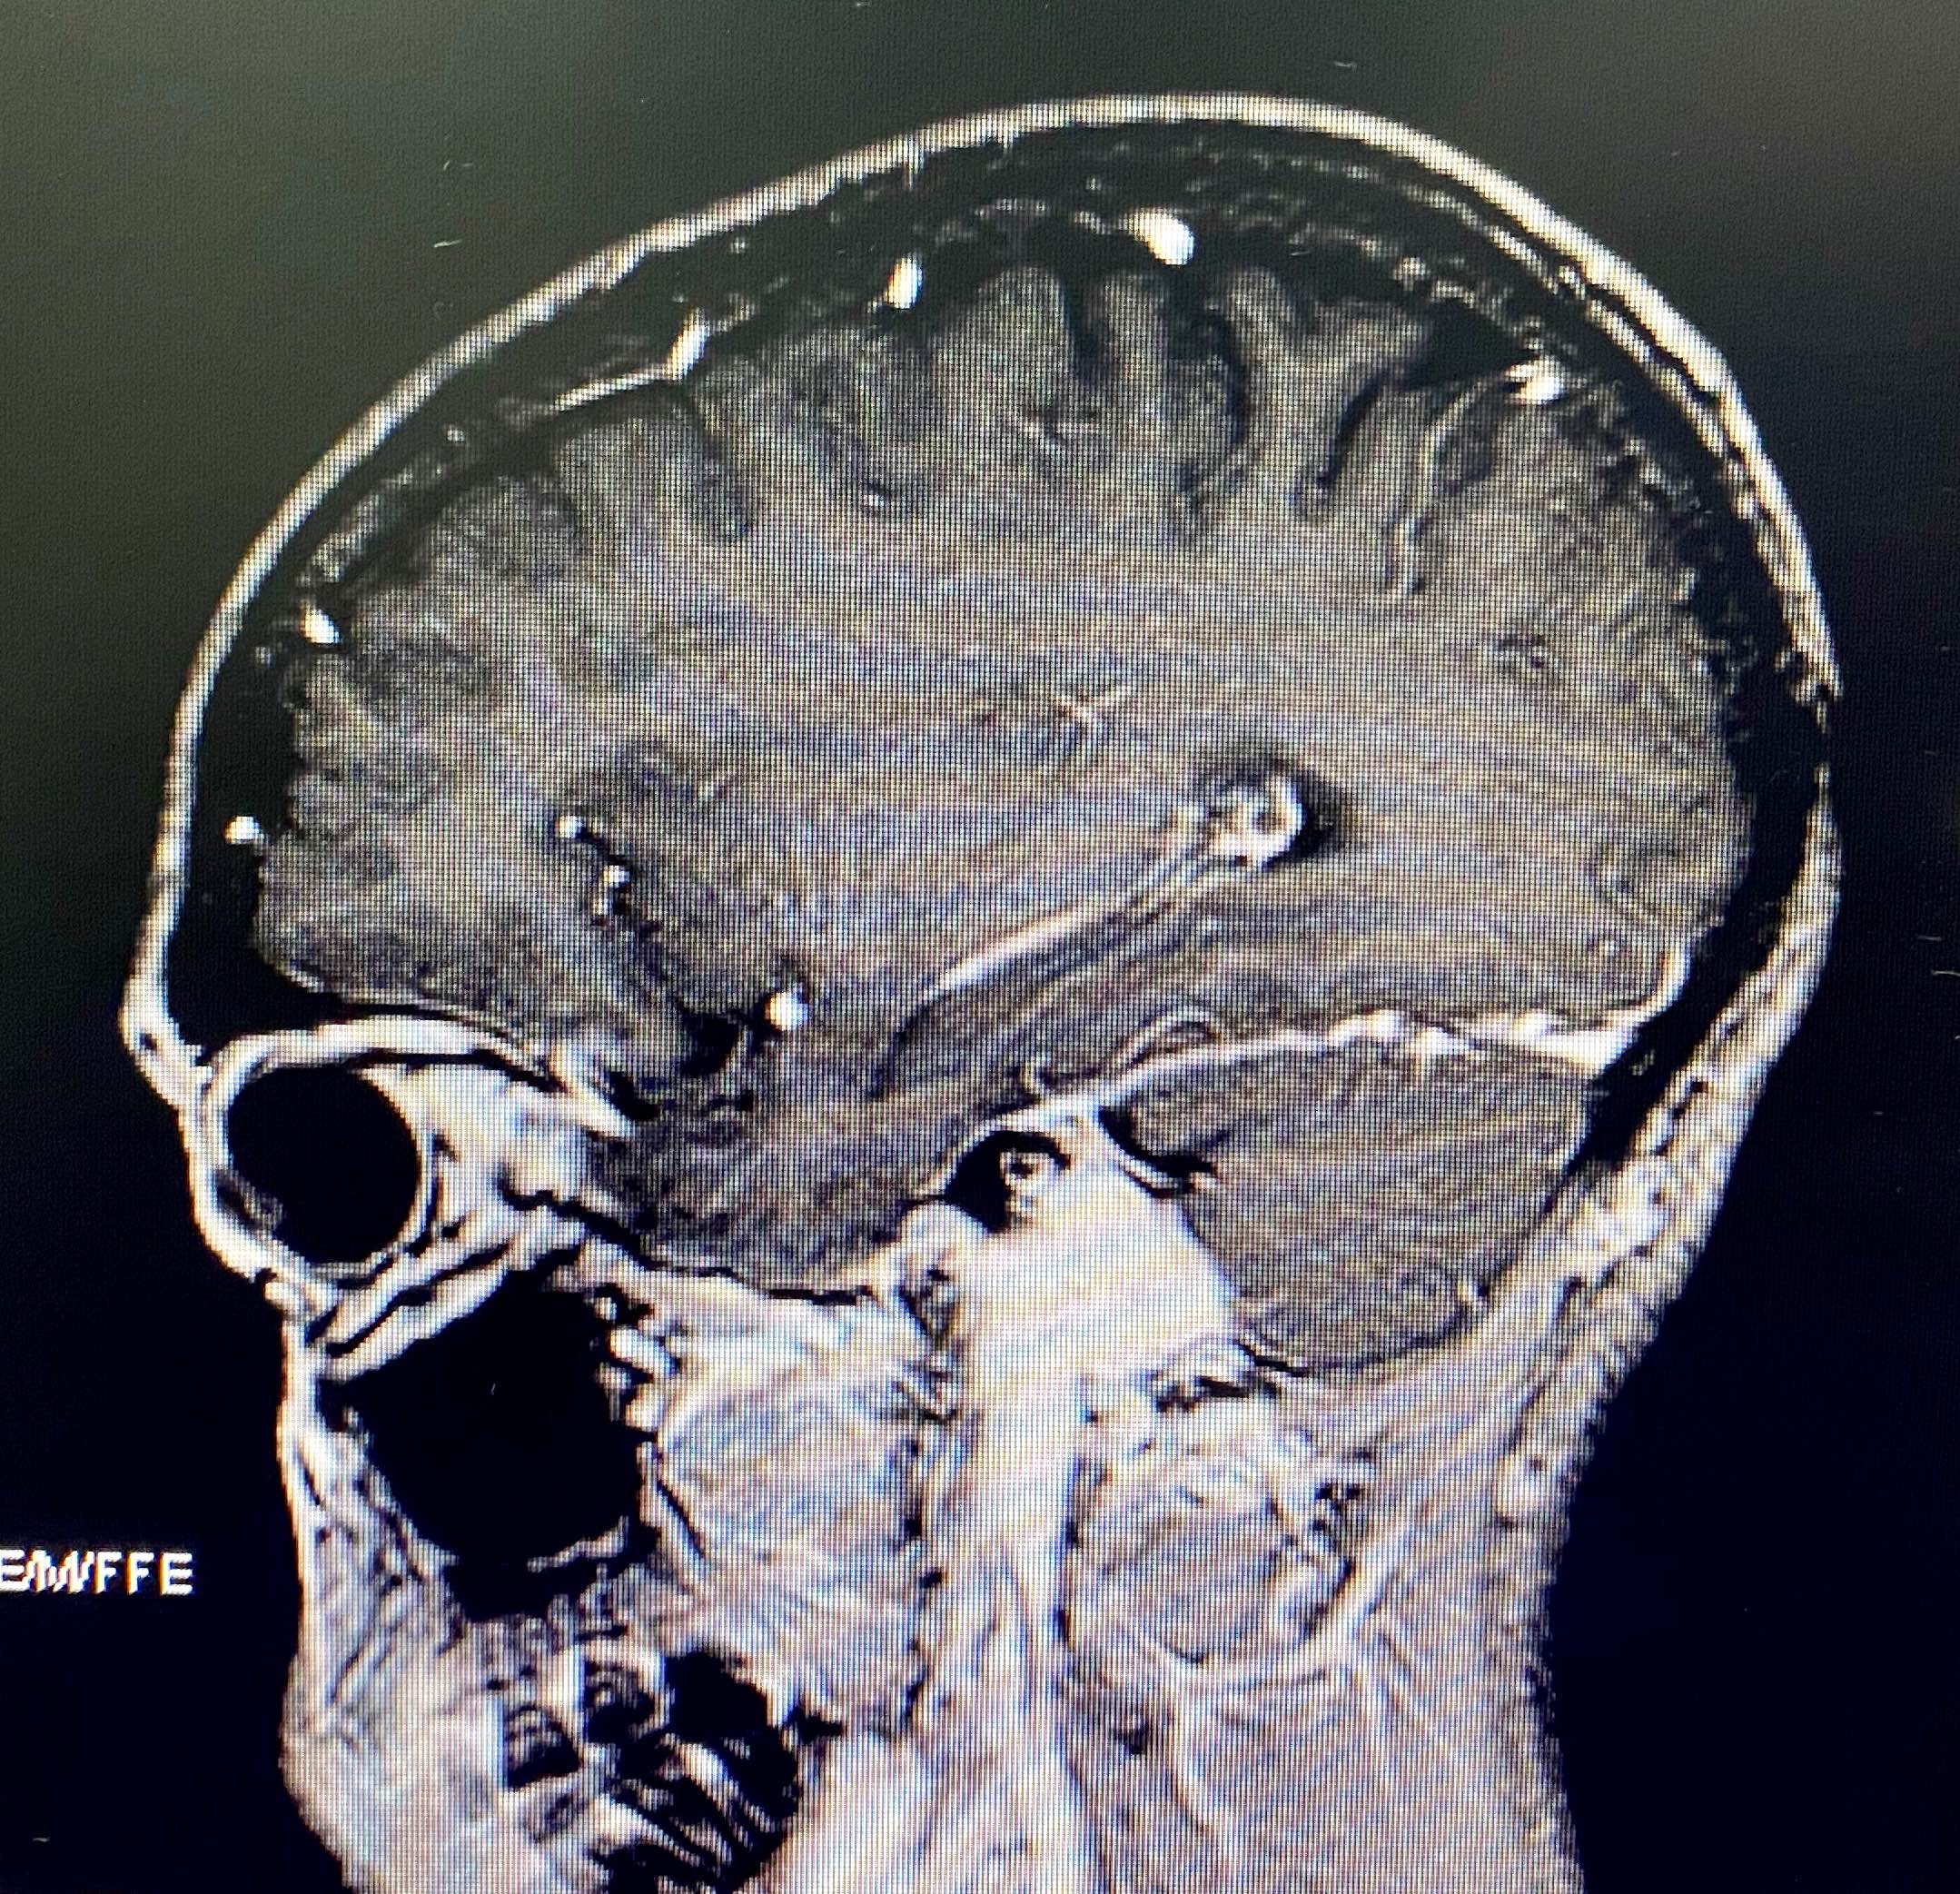

颈静脉孔区肿瘤是神经外科、耳鼻喉科和头颈外科的交界区病变。三国交界常常三不爱管。这个区域的鞘瘤和脑膜瘤可能还相对好做,但血供极其丰富的球瘤却有些麻烦,今天遇到一个中等大小球瘤,术前还是计划用神经外科的视角去处理这个病变,但为了能更好的暴露肿瘤边界以期整块切除控制出血。我们将乳突前方刚出茎乳孔的面神经先暴露出来,以便更快而安全的切除乳突尖。同时在保留半规管和外耳道完整性的前提下向前移位面神经垂直段以达到暴露肿瘤前界的目的,术中切除C-1横突,解除其对前方肿瘤的遮挡(不做椎动脉移位)。